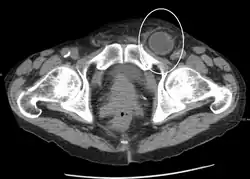

In the diagnosis of abdominal hernias, imaging is the principal means of detecting internal diaphragmatic and other nonpalpable or unsuspected hernias. Multidetector CT (MDCT) can show with precision the anatomic site of the hernia sac, the contents of the sac, and any complications. MDCT also offers clear detail of the abdominal wall allowing wall hernias to be identified accurately.[19]